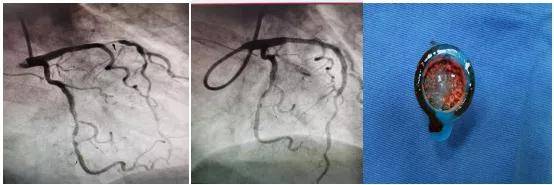

术中发现患者左冠状动脉前降支近段95%弥漫性狭窄 , 可见血栓影 , 中段80%节段性狭窄 , 远端80%节段性狭窄 , 考虑为急性左冠脉前降支近段病变为罪犯病变 , 王健副主任立刻提出:运用血栓抽吸装置对该部位进行血栓抽吸 。 随后 , 抽吸出大量红白色血栓 , 并为患者进行药物球囊扩张 。

术后患者恢复良好 , 继续规范药物治疗 , 实现了急性心肌梗死患者“有介入、无植入”的最好结果 。